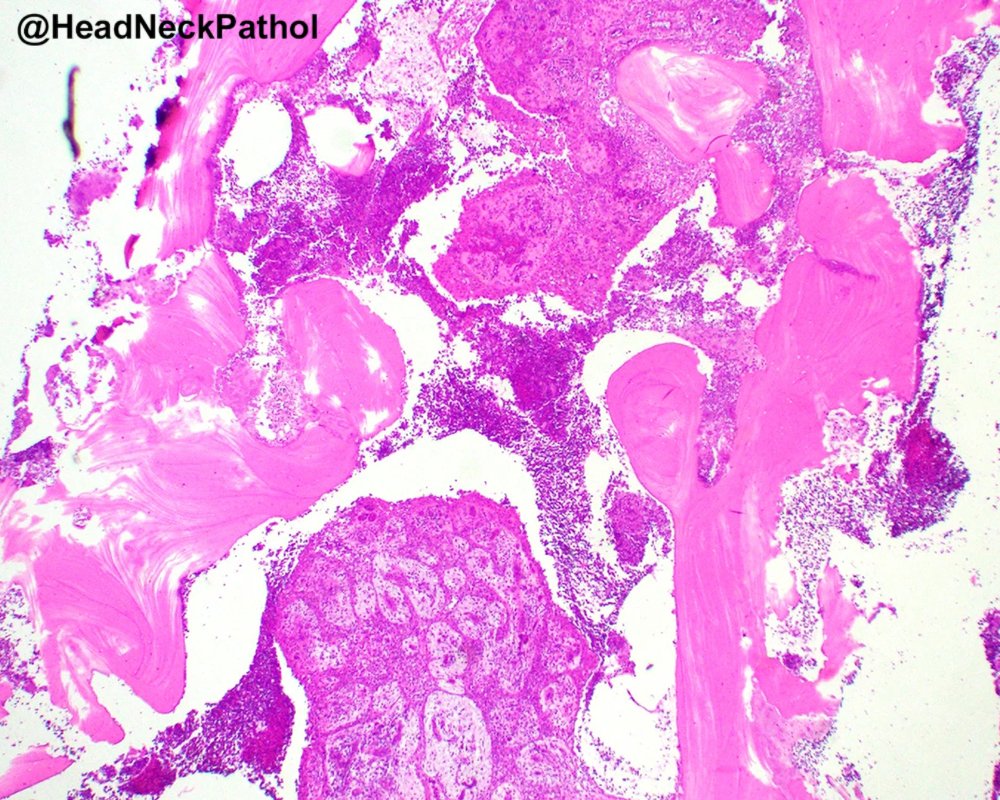

Intraductal Salivary Gland Neoplasms of the Oral Cavity: A Retrospective Case Series with Emphasis on Newly Described Entities